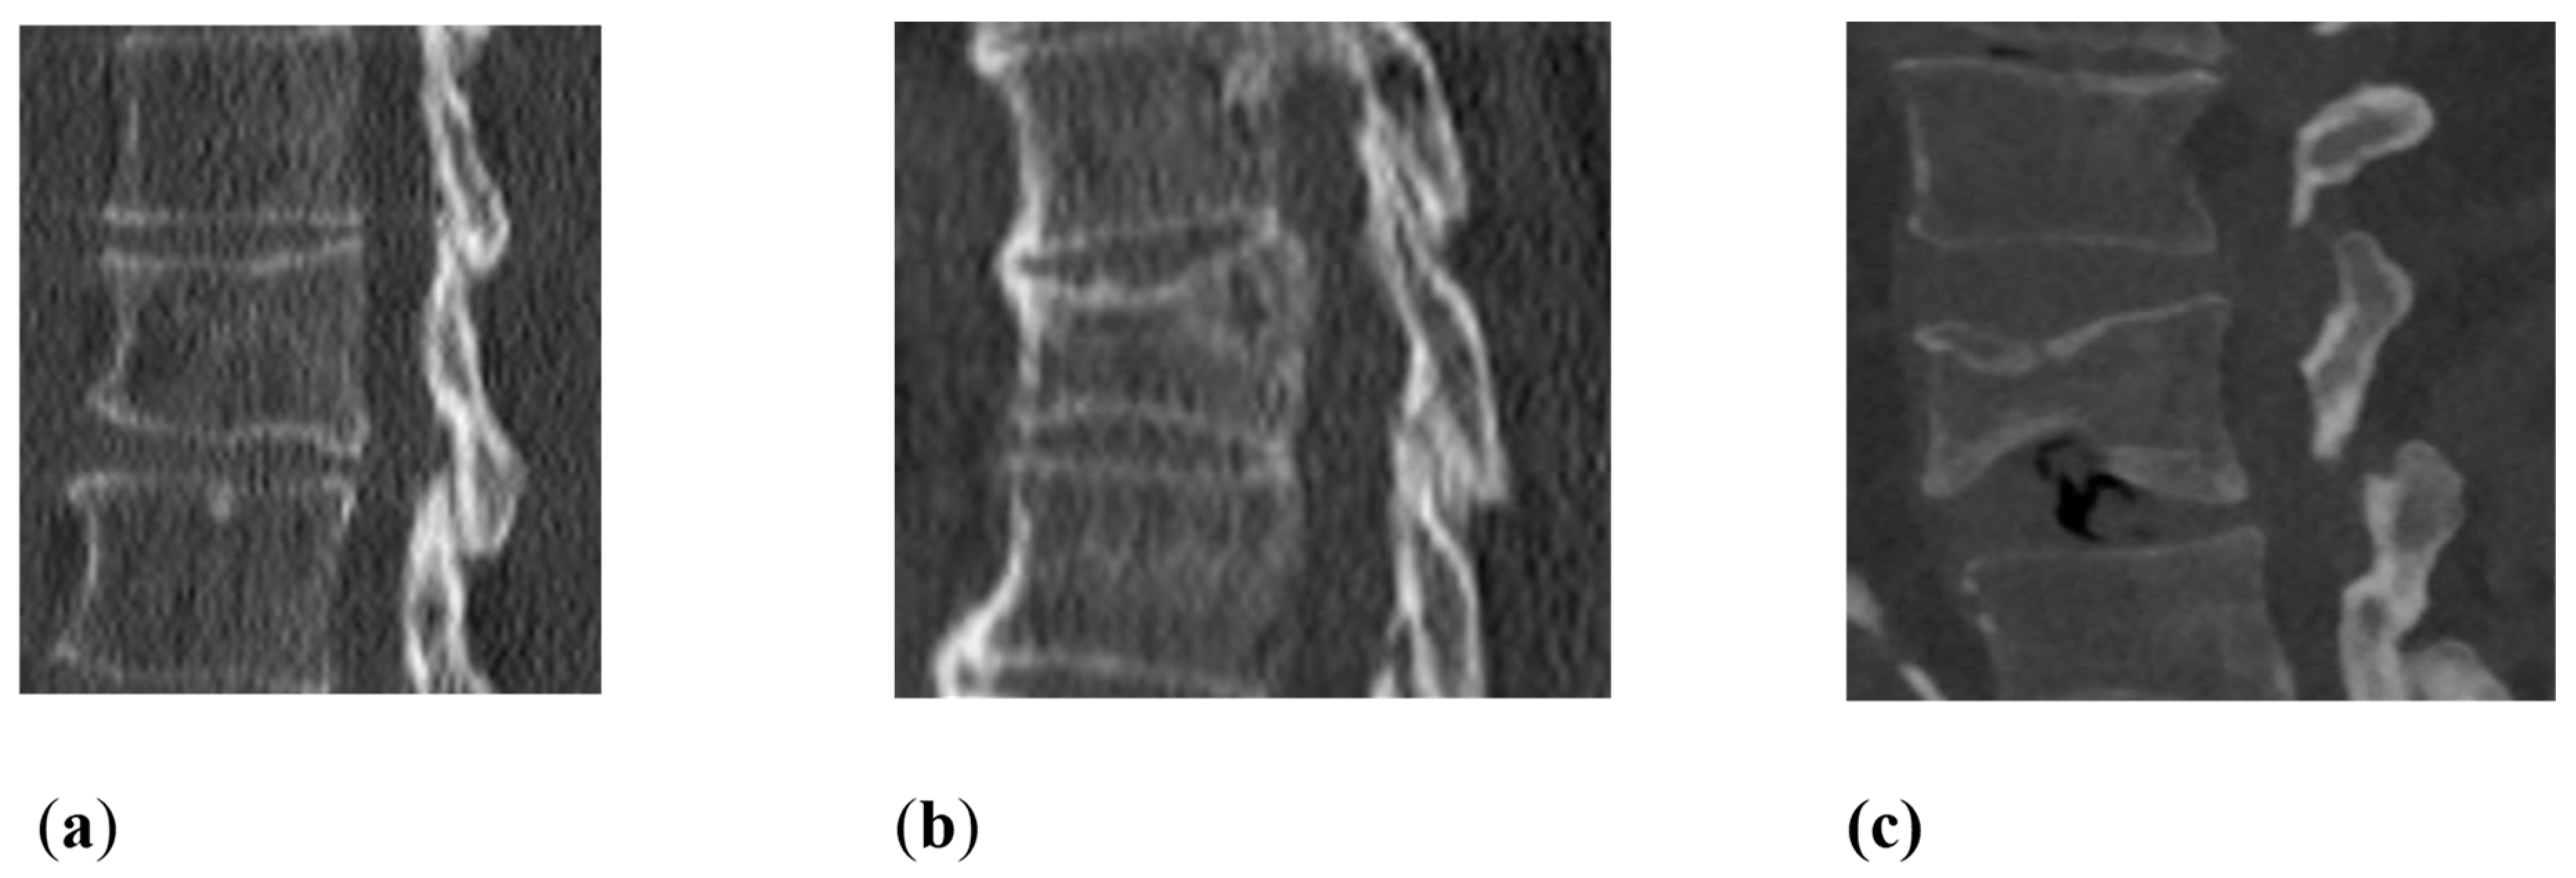

2.2. Image Analysis

| Fatty degeneration of the autochthonous back muscles | Goutallier score 0–4: